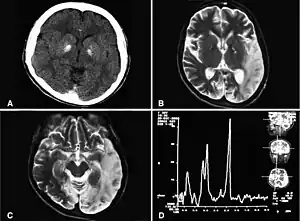

| Basal ganglia calcification, cerebellar atrophy, increased lactate; a CT image of a person diagnosed with MELAS | |

MRI: Multifocal infarct-like cortical areas in different stages of ischemic evolution, areas that do not conform to any known vascular territory. Initial lesions often occur in the occipital or parietal lobes with eventual involvement of the cerebellum, cerebral cortex, basal ganglia, and thalamus.

Lactate levels are often elevated in serum and cerebrospinal fluid. MR spectroscopy may show an elevated lactate peak in affected and even unaffected brain areas. Muscle biopsy shows ragged red fibers. However, genetic evaluation should be done first, which eliminates the need for muscle biopsy in most cases. Diagnosis may be molecular or clinical: